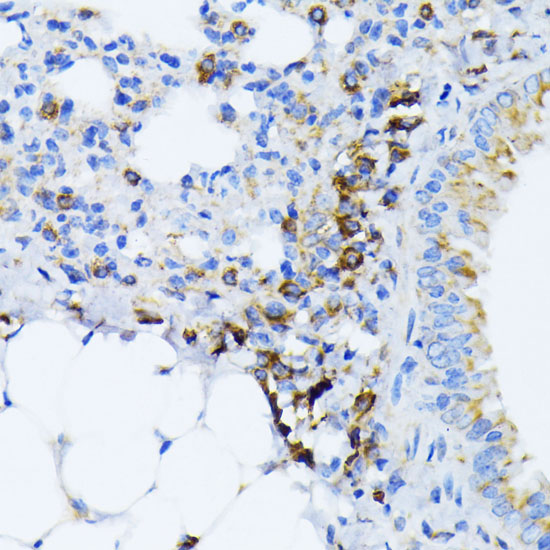

BackgroundThe protein encoded by this gene is a member of the heat shock protein 70 (HSP70) family. It is localized in the lumen of the endoplasmic reticulum (ER), and is involved in the folding and assembly of proteins in the ER. As this protein interacts with many ER proteins, it may play a key role in monitoring protein transport through the cell.

DescriptionGRP78-BiP Polyclonal Antibody. Unconjugated. Raised in: Rabbit.

ImmunogenA synthetic peptide corresponding to a sequence within amino acids 550-650 of human GRP78 / BiP (NP_005338.1)

Alternative NamesHSPA5; BIP; GRP78; HEL-S-89n; MIF2; 78 kDa glucose-regulated protein

ApplicationWB, IHC